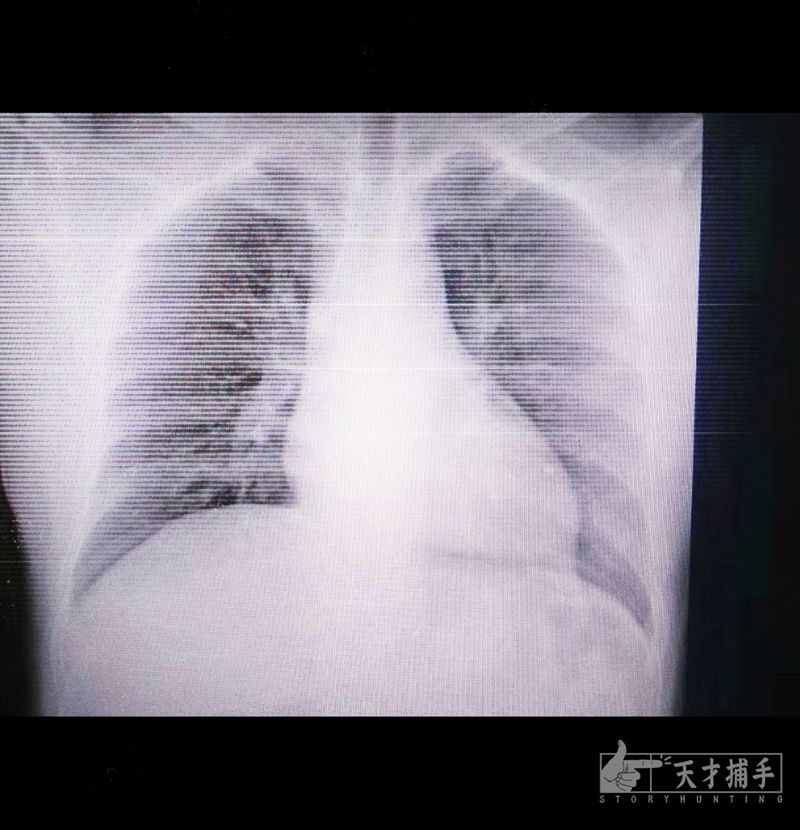

我跟大夫一起观察了图像。从图像来看,并无明显异常,是正常的健康的胸片图像。

“还可以还可以。”大夫嘴里不住念叨。

难道是虚惊一场?

我稍稍放心,却也未完全放松下来,毕竟床旁胸片漏诊率相对是高的。

扫描后,我看了一眼图像,心里一噔——

肺部有很多处片状的高密度影,样子发白,却又与之前看到过的感染征象不同。

因为读片毕竟不是我的专业,我只能通过经验感觉这次图像有所不同。

我打电话给诊断同事,今天值班的同事是刚刚入职的小哥哥,他在系统上看了片子后也表示之前未看到过这样的图像,只能确定感染,还无法确定是否是新型冠状病毒。

我打开丁香园,尝试着寻找之前是否有类似病例的CT图像,万幸找到一例。对比了一下,除了感染面积不同,均像是磨玻璃的样子。是病毒性肺炎CT常有的特点。